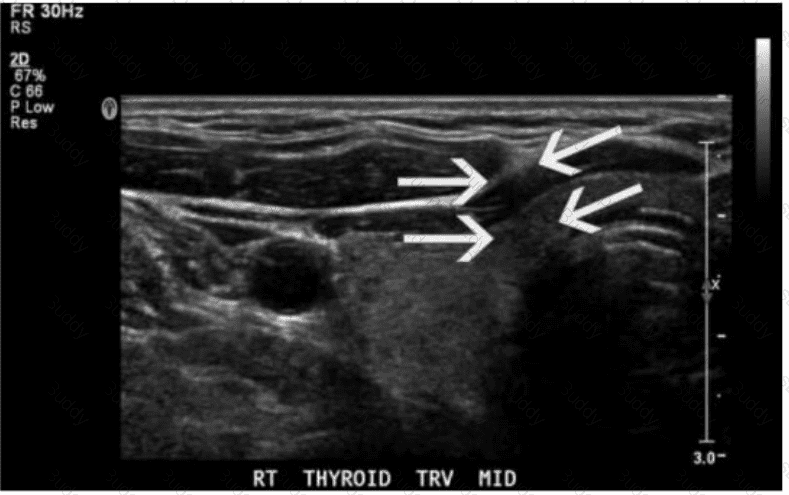

Which lymph node shape is concerning for malignancy in the post-thyroidectomy neck?